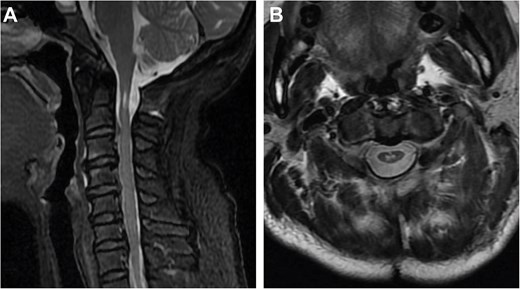

We used a posterior cervical approach to resect the posterior arch of C1. There were no intraoperative complications during the procedure. The patient’s symptoms improved dramatically following the operation. The cervical spinal cord lesion showed no evidence of progression on the 18-month follow-up MRI (Fig. 4A and B). To present, the patient is stable, with no symptoms or signs of recurrence.

Two-year postoperative MRI results. (A) Sagittal T2-weighted MRI. (B) Axial T2-weighted MRI.